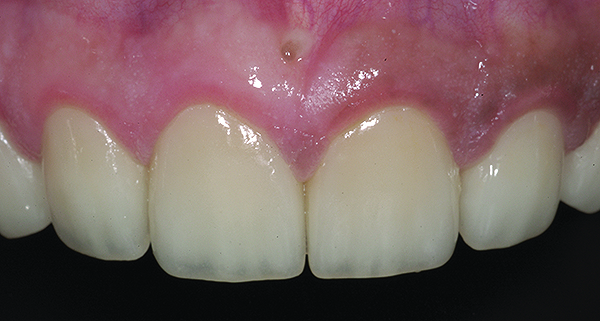

Figure 16. Anterior final restorations bonded.

Figure 16

The anterior restorations were fabricated with low-translucency lithium-disilicate ingots and layered in the incisal half to provide the desired internal characteristics in accordance with the patient’s age. The final anterior restorations were then tried-in and verified for marginal fit, esthetics, and phonetics. After the patient’s approval, they were bonded using dual-cured resin cement (Variolink® II, Ivoclar Vivadent) (Figure 16). Because the enamel in such cases is already compromised, bonding can become clinically unpredictable. A self-etching primer was used on the teeth, followed by a bonding agent (Clearfil™ ST Bond, Kuraray Dental, www.kuraraydental.com) that was light-cured for 20 seconds. The intaglio of the crowns was prepared by etching with 9% buffered hydrofluoric acid for 60 seconds and silanating them to achieve optimum bonds to the resin cement.18